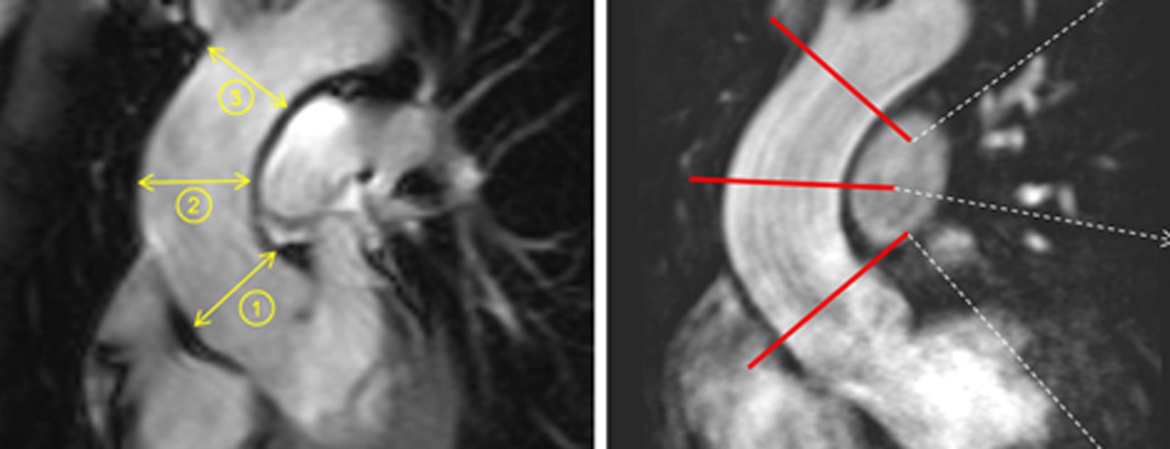

Tardu Özkartal, Alexander Breitenstein, Ardan M. Saguner, Devdas T. Inderbitzin, Markus J. Wilhelm, Stefano Benussi, Francesco Maisano, Thomas F. Lüscher, Frank Ruschitzka, Jan Steffel (Author)